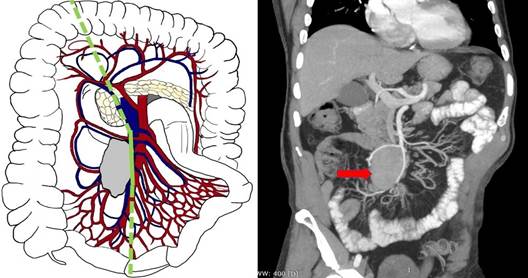

Третий В тип (уровень III по Ohrvall) - вовлечение стволов ВБА и/или ВБВ дистальнее ветвления a. et v. ileocolica. В подобных случаях выполняем резекцию подвздошной кишки с перевязкой соответствующих стволов ВБА и ВБВ выше уровня поражения, с сохранением a. et v. Ileocolica, что позволяет не резецировать восходящий отдел толстой кишки (рис. 4). При этом перевязываются не менее трёх радиальных ветвей ВБА первого порядка, что приводит к протяженной резекции кишки.

Рис. 4. Третий В тип (уровень III) - вовлечение стволов и ветвей ВБА/ВБВ дистальнее ветвления a. et v. ileocolica